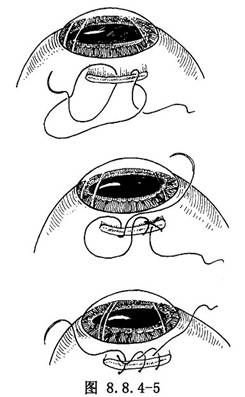

爲使鞏膜暴露充分,在肌肉止端處縫一個三鎖環牽拉線(圖8.8.4-5)。